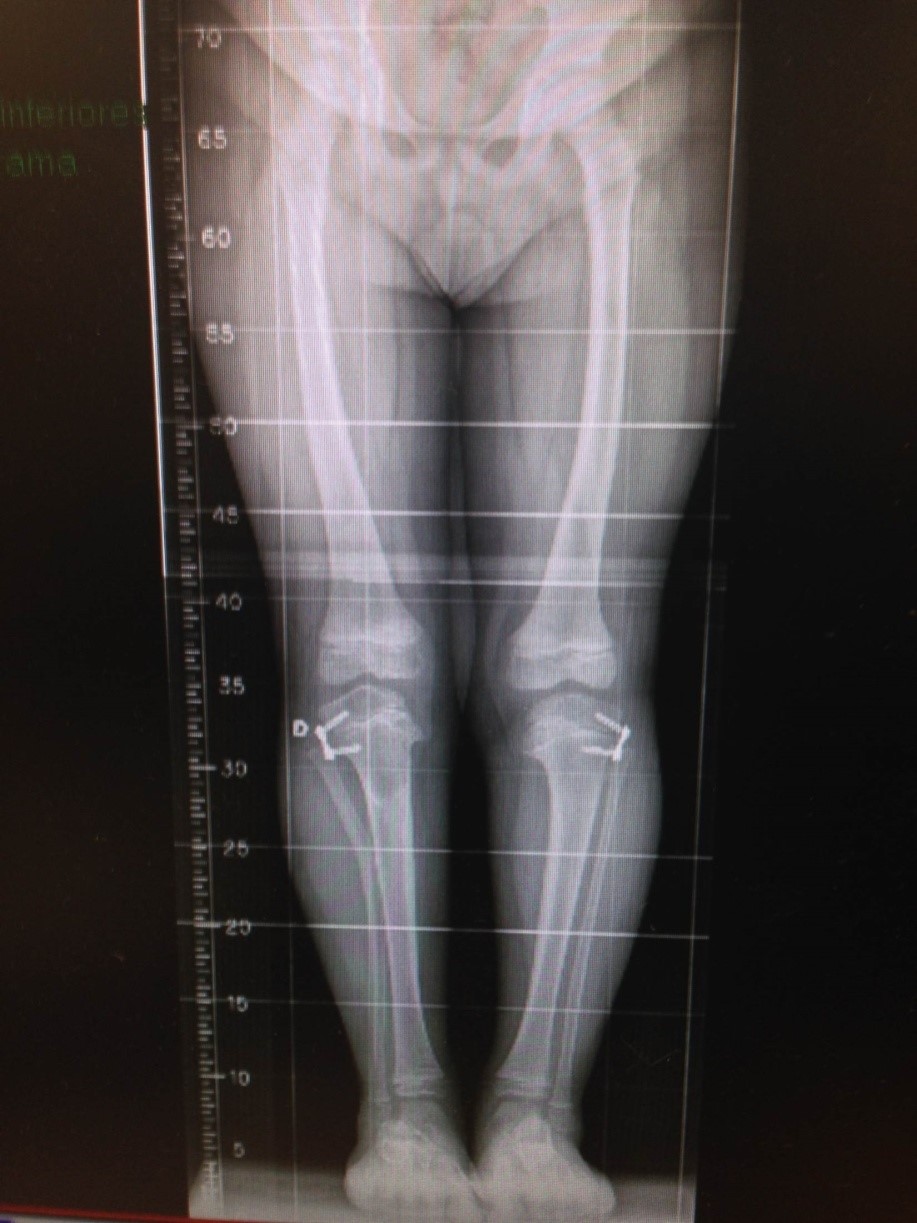

Estudos radiográficos podem auxiliar o médico a avaliar a forma dos membros, registrá-los para comparação futura durante o crescimento, estudar defeitos ósseos ou articulares, com correspondência a várias doenças que podem causar tais alterações (figuras 3 A e 3 B).

Figura 4. Joelhos varos por doença hereditária (Blount).